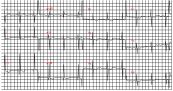

Xuất huyết dưới nhện là tình trạng máu bị rò rỉ chảy vào khoảng trống giữa não và màng bao quanh (màng não). Nếu như không được cấp cứu kịp thời, tình trạng này sẽ có thể gây ra các tổn thương nghiêm trọng tại não và thậm chí là tử vong. Vậy trên điện tâm đồ, bệnh lý này thể hiện như thế nào? Mời các bạn tham khảo bài viết dưới đây để hiểu rõ hơn nhé!